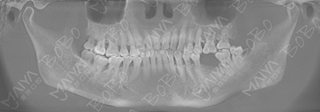

口腔ct全景片

术后口腔全景ct